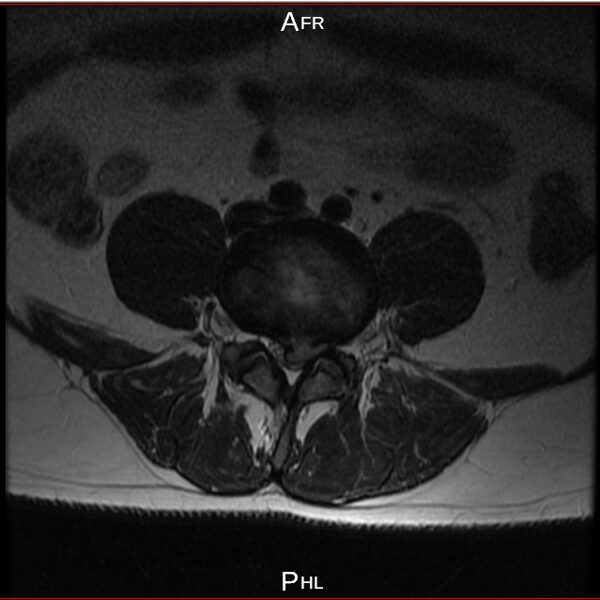

I have a lower spine problem, herniated disk and was using acupuncture (acupuncture is really good to control your musculus and controlling you like a robot) treatments with a Chinese doctor, first time all was perfect, but second time looks like happen mistake, you will be able to see this on pictures from private MRI scan– nuclear magnetic resonance that I have organised for myself. My left leg was just bone and skin, I lost all the musculus, because was not able to feed the main nerve responsible for keeping the proper function of the whole leg – I was parallelized. Pain is 24/7, 10 out of 10. At Royal infirmary hospital Edinburgh where I was hospitalized was giving me crazy amount of pain killers and very strong, that never helped. The doctors at the hospital they did great job providing me with modern technology to prevent the rest of the disk to slipping out to obtain the so-called calcification. All NHS staff did great job looking after me there. By 98% of the Doctors from around the world that I have managed to contact told me, that I have to make operation and there is no chance this to be sorted out other way. Well I have spent six months from my life and thanks god I had the finance to do that, trying to avoid operation. I have meet the right people to help me and expand my knowledge and I managed to avoid operation. Thanks to nature too. This situation get me to start learning a lot for human being anatomy and physiology, also reflexology, trigger points, blood, tocsins, minerals, how brain is responsible and reacting and much more…